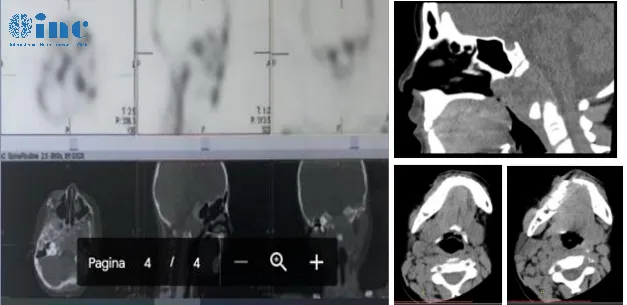

6岁女性患儿萌萌出现颈部活动受限症状,父母最初注意到患儿颈部转动不灵活,活动度较前下降。患儿既往活泼好动,喜爱舞蹈表演,但近一个月出现颈部活动障碍,头部不自主向一侧倾斜,无外伤史。伴随症状包括咽部红肿和扁桃体肿大影像学检查显示枕骨斜坡区骨质破坏,鉴别诊断考虑朗格汉斯细胞组织增生症(LCH)或脊索瘤。

INC国际神经外科专家Sebastien Froelich教授(法国巴黎狄德罗大学Lariboisiere医院神经外科教授,前世界神经外科联合会WFNS颅底手术委员会主席)评估认为:影像学表现符合脊索瘤特征,但肿瘤在T2序列上信号不高,增强扫描显示浸润性生长方式。提示可能为侵袭性较强的脊索瘤类型。

肿瘤累及范围包括双侧岩尖(左侧为主),向下延伸至双侧颈静脉孔和舌下神经管,破坏双侧髁状突约50%,此解剖改变可解释患儿斜颈症状。同时发现肿瘤向左下浸润至C1椎体水平。专家建议术中进行病理检查,若确诊脊索瘤则继续实施肿瘤切除手术。